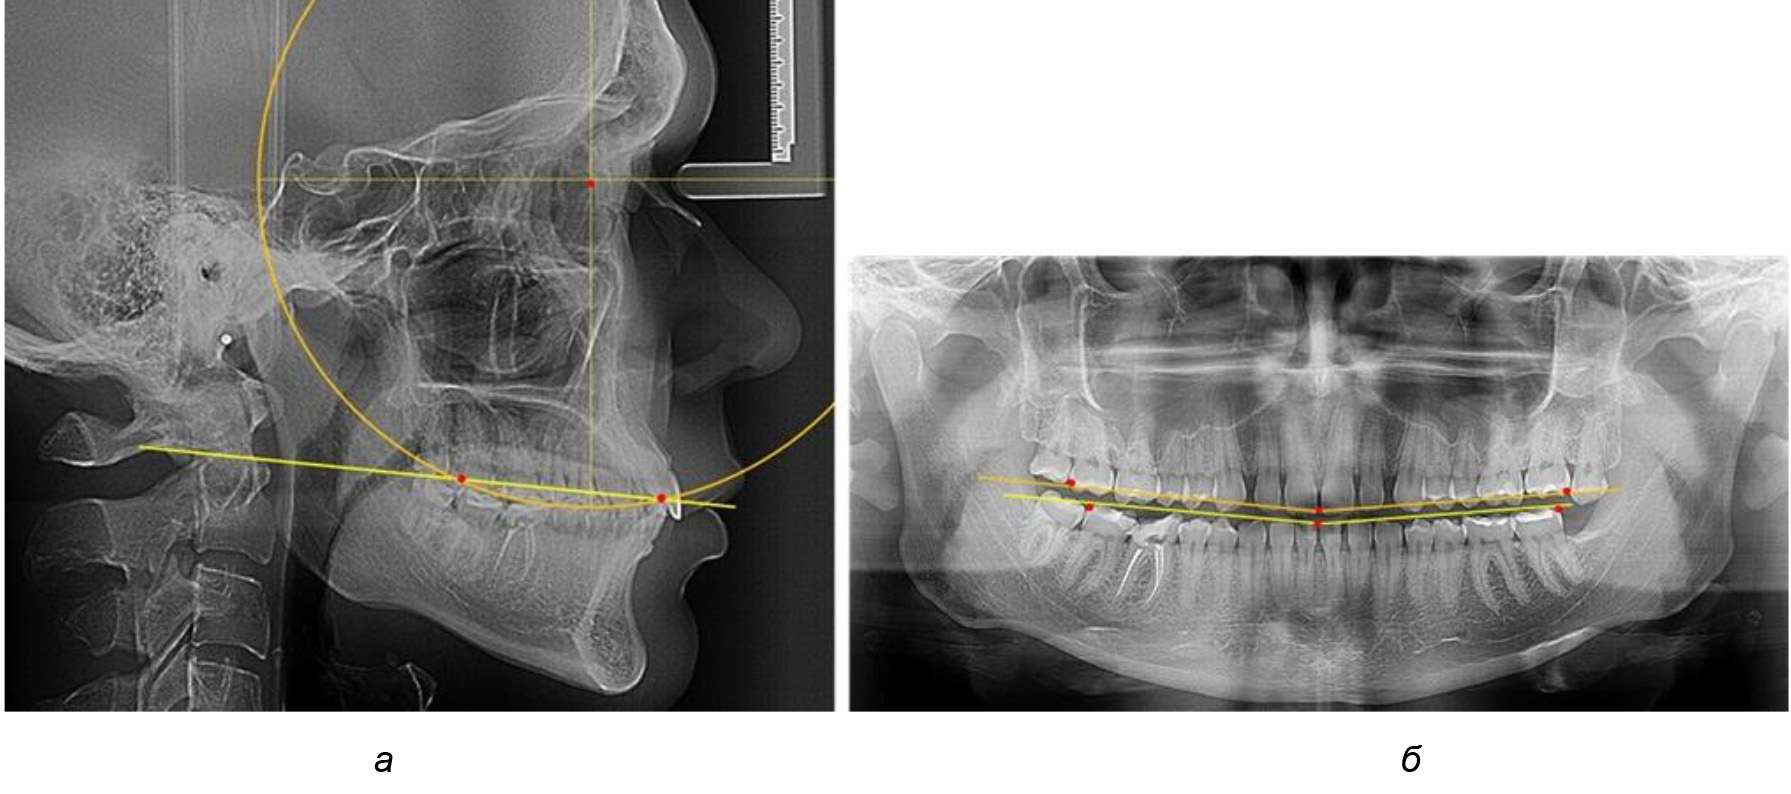

После лечения пациентов техникой «прямой» дуги, так же как и в 1-й подгруппе, было отмечено увеличение сагиттального размера окклюзионной лини в среднем на (2,38 ± 0,83) мм. Окклюзионная линия практически касалась окклюзионного контура всех жевательных зубов, и отмечалось практически полное отсутствие кривой Spee, так же как и у людей 1-й подгруппы 2-й группы (рис. 6).

Рис. 6. Особенности ТРГ при оптимальной кривой Spee до лечения (а) и после лечения (б) техникой «прямой» дуги

Таким образом, проведенное лечение техникой «прямой» дуги способствует нормализации окклюзионного равновесия и торку передних зубов, однако не соответствует оптимальному окклюзионному статусу, характеризующему физиологическую окклюзию. При этом величина нижнечелюстного угла оставалась на прежнем уровне.